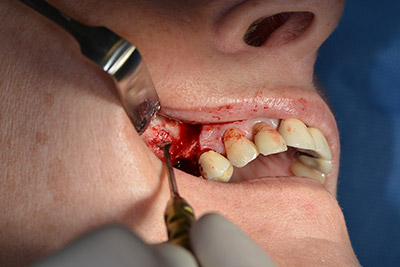

The next step was the sinus floor elevation with simultaneous implantation. The Implantmed also had a presetting at the first position for the buccal fenestration of the maxillary sinus wall.

The fenestration was prepared at 35,000 rpm and then the nasal mucosa were prepared in the cranial direction (Fig. 13 to 14).